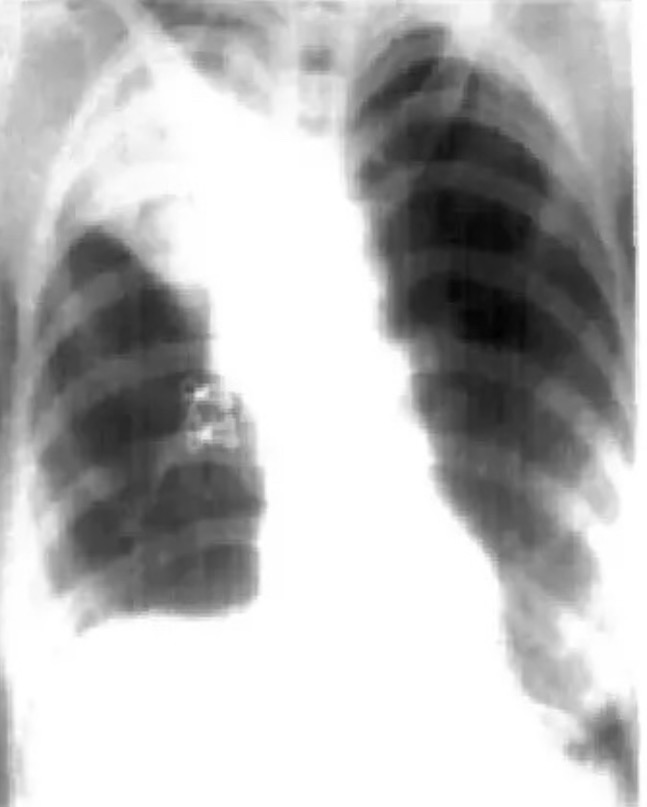

Figure 1. Рентгенограмма грудной клетки, показывающая коллапс правой верхней доли -уплотнение легкого.